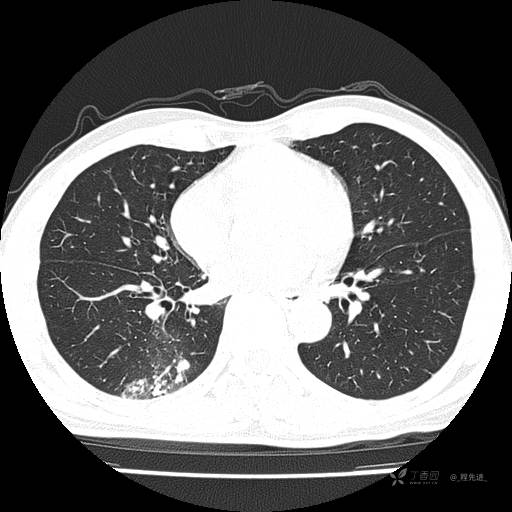

2月特别精彩病例|咳嗽、咳痰20余天,典型病例分享【结果已公布】

患者年龄:51岁

主诉:咳嗽、咳痰20余天

简要病史:20余天前开始出现咳嗽、咳痰症状,阵发性刺激性咳,白色粘痰,不易咳出,无发热,无咯血,无恶心、呕吐等不适,未诊治,咳嗽、咳痰症状持续存在。

体格检查:T:36.3 ℃ P:79 次/分 R:20 次/分 BP:128/64 mmHg,神志清楚,呼吸平稳,双肺呼吸音粗,右下肺闻及细湿性啰音。心率79次/分,节律整齐,各瓣膜听诊区未闻及病理性杂音。腹部未见异常,双下肢无水肿。

辅助检查:我院门诊胸部CT示:如下。心电图:窦性心律;正常心电图。